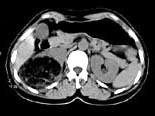

问题 女,53岁,右侧轻度腰背酸痛,行CT检查,如图所示,可能的诊断为 ( )

选项 A、右腹膜后脂肪瘤 B、右肾血管平滑肌脂肪瘤 C、右肾上腺腺瘤 D、右肾上腺嗜铬细胞瘤 E、右肾上腺髓样脂肪瘤

答案 E